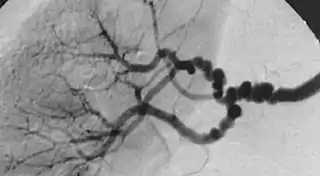

La displasia fibromuscular es una enfermedad poco frecuente de causa desconocida que afecta a las arterias de calibre pequeño y mediano provocando disminución de su luz y en ocasiones formación de aneurismas. Los síntomas son variables dependiendo del territorio afectado, cuando causa estenosis de la arteria renal provoca hipertensión renovascular, por el contrario si actúa sobre la arteria carótida causa accidente cerebrovascular por disminución del riego cerebral. El diagnóstico se sospecha por los síntomas y se confirma por angiotomografía computarizada, angiorresonancia magnética o angiografía, donde se observan unos vasos con estrechamientos y dilataciones alternantes según un patrón que se ha descrito como collar de perlas. El tratamiento recomendado es la angioplastia transluminal.[1][2][3]

![]() Angiografía en un caso de displasia fibromuscular | ||